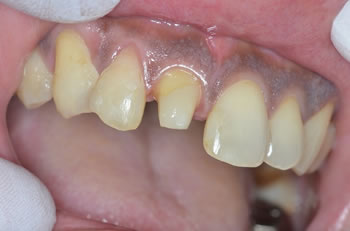

僕のお友達なのですが、事故で前歯がポッキリと折れてしまい、、、

「歯抜けになったので何とかして~!」との事で、、、

すでに露髄していたので根管治療して、ファイバーコアが装着されてます! |

見事にパックリと折れてしまい、、、かわいそうです、、、

お隣の歯も歯先が欠けて、動いていたので固定中です! |